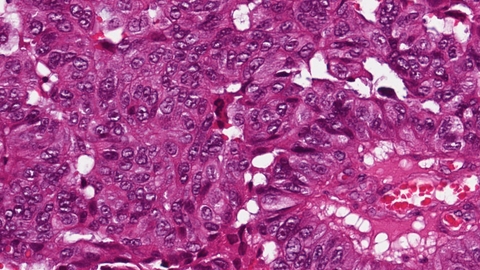

Genomics yields a new understanding of pancreatic cancer

A breakthrough study of over 450 pancreatic cancer genomes showed that pancreatic cancer can be divided into four distinct diseases, each of which many respond differently to therapies, meaning this study has implications for how clinicians assess and treat pancreatic cancer